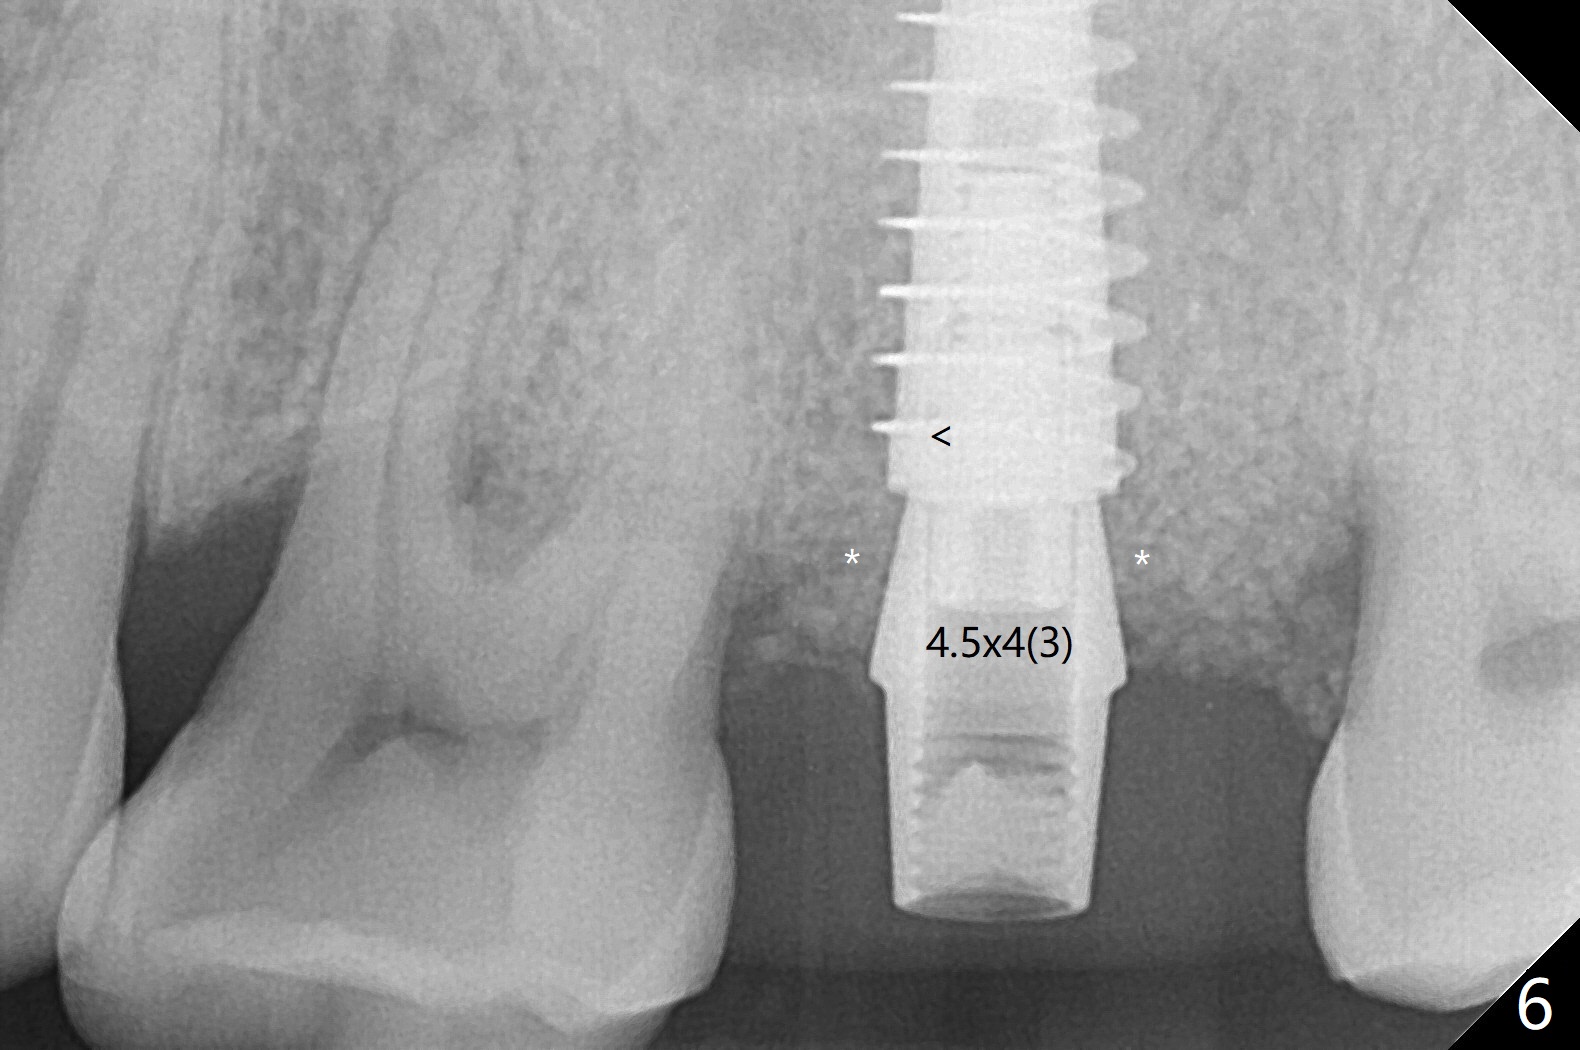

At #15, the sinus floor is initially perforated with modified drill sequence. With placement of PRF and bone graft in the osteotomy, the same 4.5x11 mm dummy implant is inserted to start sinus lift (Fig.4 *). When the dummy implant is removed, more bone graft is placed into the osteotomy and pushed into the sinus with the 5x11 mm final implant (Fig.5). Second round of bone graft is placed next to the implant before placing a 4.5x4(2) mm abutment, but the latter appears not to be seated completely, as indicated by the arrowhead. After use of 6 mm profile drill, a 4.5x4(3 (cuff)) mm abutment is able to be seated apparently completely without a gap (Fig.6 <). The third round of bone graft (Fig.6 *) is placed around the abutment to make sure that the underlying implant is fully covered to reduce periimplantitis in the future. The bone graft around the abutment disappears most coronally, while that around the implant remains 4 months postop (Fig.7). The implant is stable.